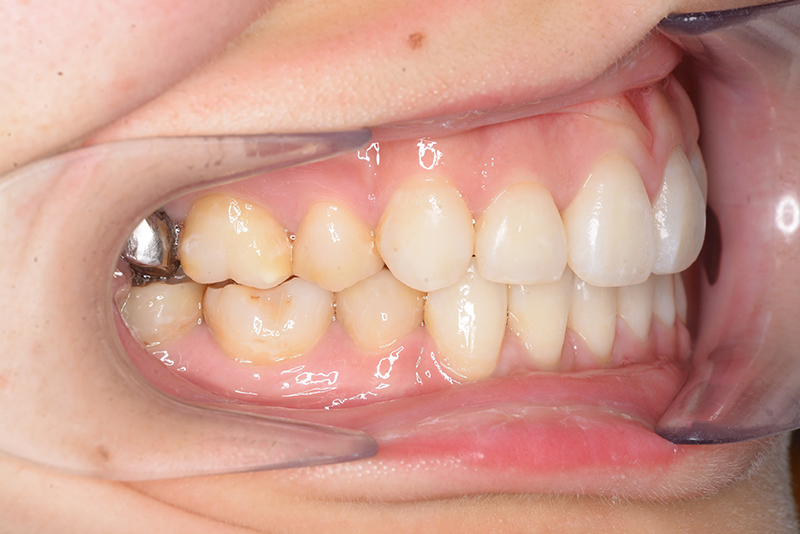

初診時

FP・IOP

口腔内所見 over jet 4.0mm、over bite 2.0mm、臼歯関係Ⅰ級、犬歯関係Ⅱ級で上顎前歯は唇側傾斜を呈しており、上下顎前突の様相を呈していた。